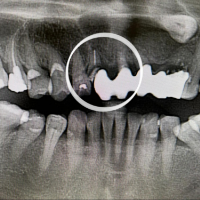

症例4

治療方法 ダイレクトボンディング法

治療期間 1日

治療費用 ダイレクトボンディング 1歯 ¥44,000×4本 ¥176,000(税込)

治療の副作用.リスク 歯を削る必要がある

材質の経年劣化がある

長期的に安定しない

ダイレクトボンディング法

前歯の黒い線が歯のヒビでは?というお悩みで来院されました。矢印部分の黒い線は、歯のヒビではなく詰め物と歯の間の境目に入り込んだ着色が原因です。このケースでは、劣化した詰め物を削ってダイレクトボンディング法で治療を行いました。黒い線の部分と、左側の歯のすき間、中心2本の前歯の詰め物も同時に治しています。